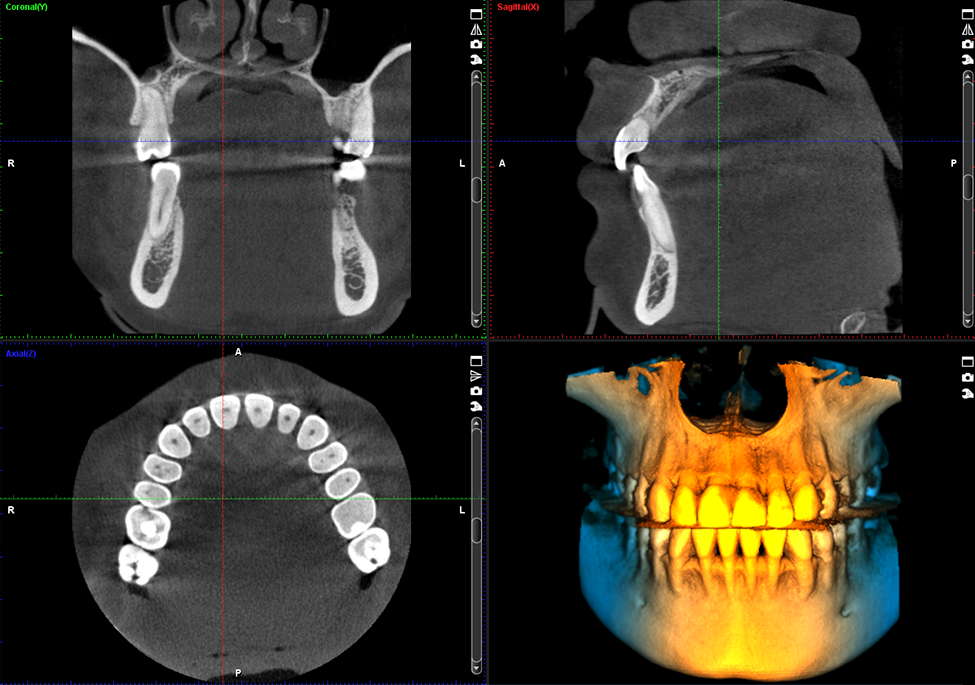

See every detail of your smile with advanced 3D imaging technology. Planmeca ProMax® 3D CBCT allows our dentists to visualize your teeth, jaw, nerves, sinuses, and bone structure in one highly accurate scan to ensure precise diagnosis and treatment planning.

Planmeca ProMax 3D is an advanced, all-in-one dental X-ray system that uses Cone Beam Computed Tomography (CBCT) to capture detailed 3D images of teeth, bones, and soft tissues in a single scan.

It combines 3D imaging with 2D panoramic and cephalometric scans in a single unit, providing comprehensive diagnostics for implantology, orthodontics, and oral surgery. This system is designed with patient safety in mind, offering precise imaging with low radiation exposure.

The Planmeca ProMax® 3D CBCT captures your entire dentition from jaw to jaw in one comfortable scan. This gives your dentist a complete view of your oral anatomy without needing multiple X-rays.

The Planmeca ProMax® 3D CBCT captures your entire dentition from jaw to jaw in one comfortable scan. This gives your dentist a complete view of your oral anatomy without needing multiple X-rays.

Planmeca ProMax® 3D CBCT makes imaging fast, comfortable, and precise. One scan provides a full view of your mouth, jaw, and surrounding structures, eliminating multiple exposures. This means safer diagnosis, faster planning, and better treatment results.

Planmeca CBCT (Cone Beam Computed Tomography) is an advanced 3D imaging system that captures highly detailed views of your teeth, jaw, bone, nerves, and sinuses in a single scan. It allows our dentists to diagnose and plan treatment with exceptional accuracy.

Traditional X-rays only show flat, 2D images. Planmeca CBCT creates a full 3D digital model of your mouth. This allows dentists to see hidden problems such as bone loss, infections, nerve locations, impacted teeth, and root fractures that regular X-rays can’t detect.